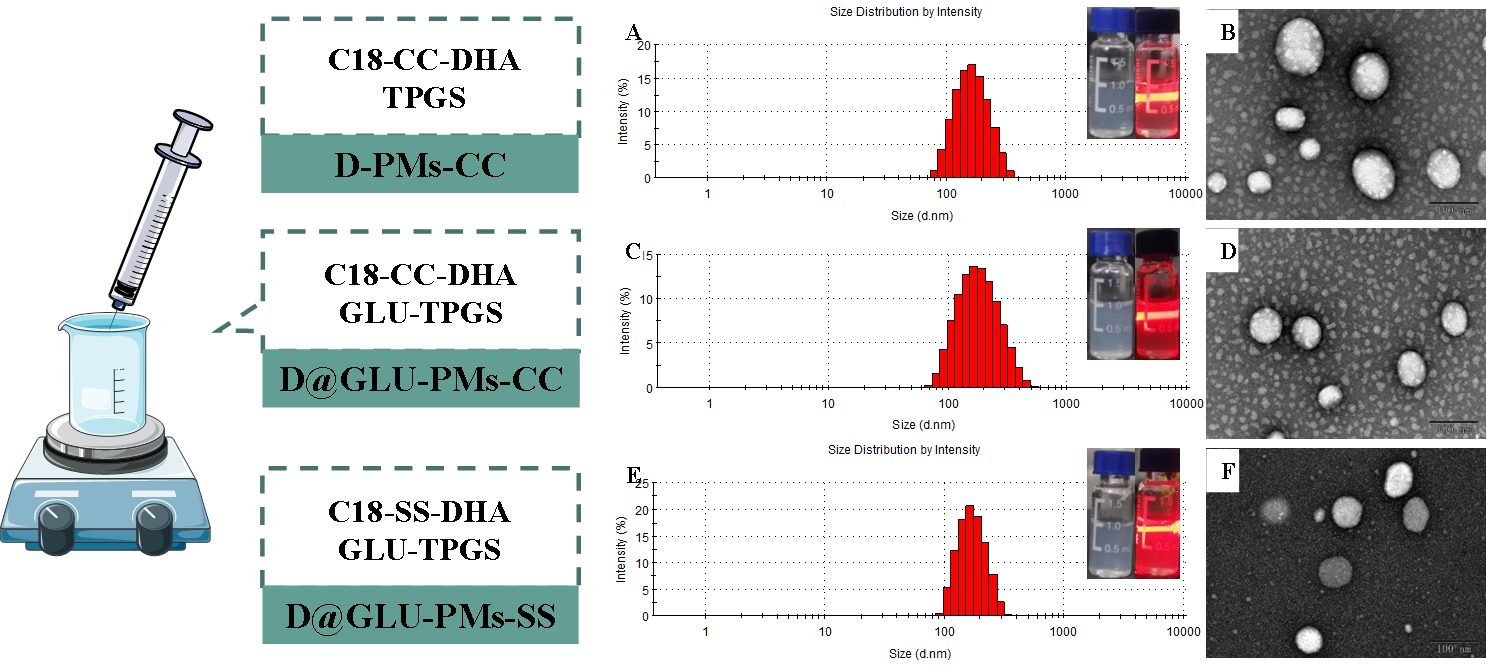

图1 D-PMs-CC(A����、B)���、D@GLU-PMs-CC(C���、D)和D@GLU-PMs-SS(E�����、F)的粒径分布���、透射电镜及外观图

为了将更多的药物被转运至疟原虫内����,在本研究中����,以二硫键为连接臂的双氢青蒿素-十八胺偶联化合物为基础��,加入葡萄糖修饰的TPGS-GLU作为稳定剂���,采用纳米沉淀法制备了无葡萄糖基修饰的非还原响应微粒(D-PMs-CC)��、葡萄糖基修饰的非还原响应微粒(D@GLU-PMs-CC)和葡萄糖基修饰的还原响应微粒(D@GLU-PMs-SS)(图1)��。